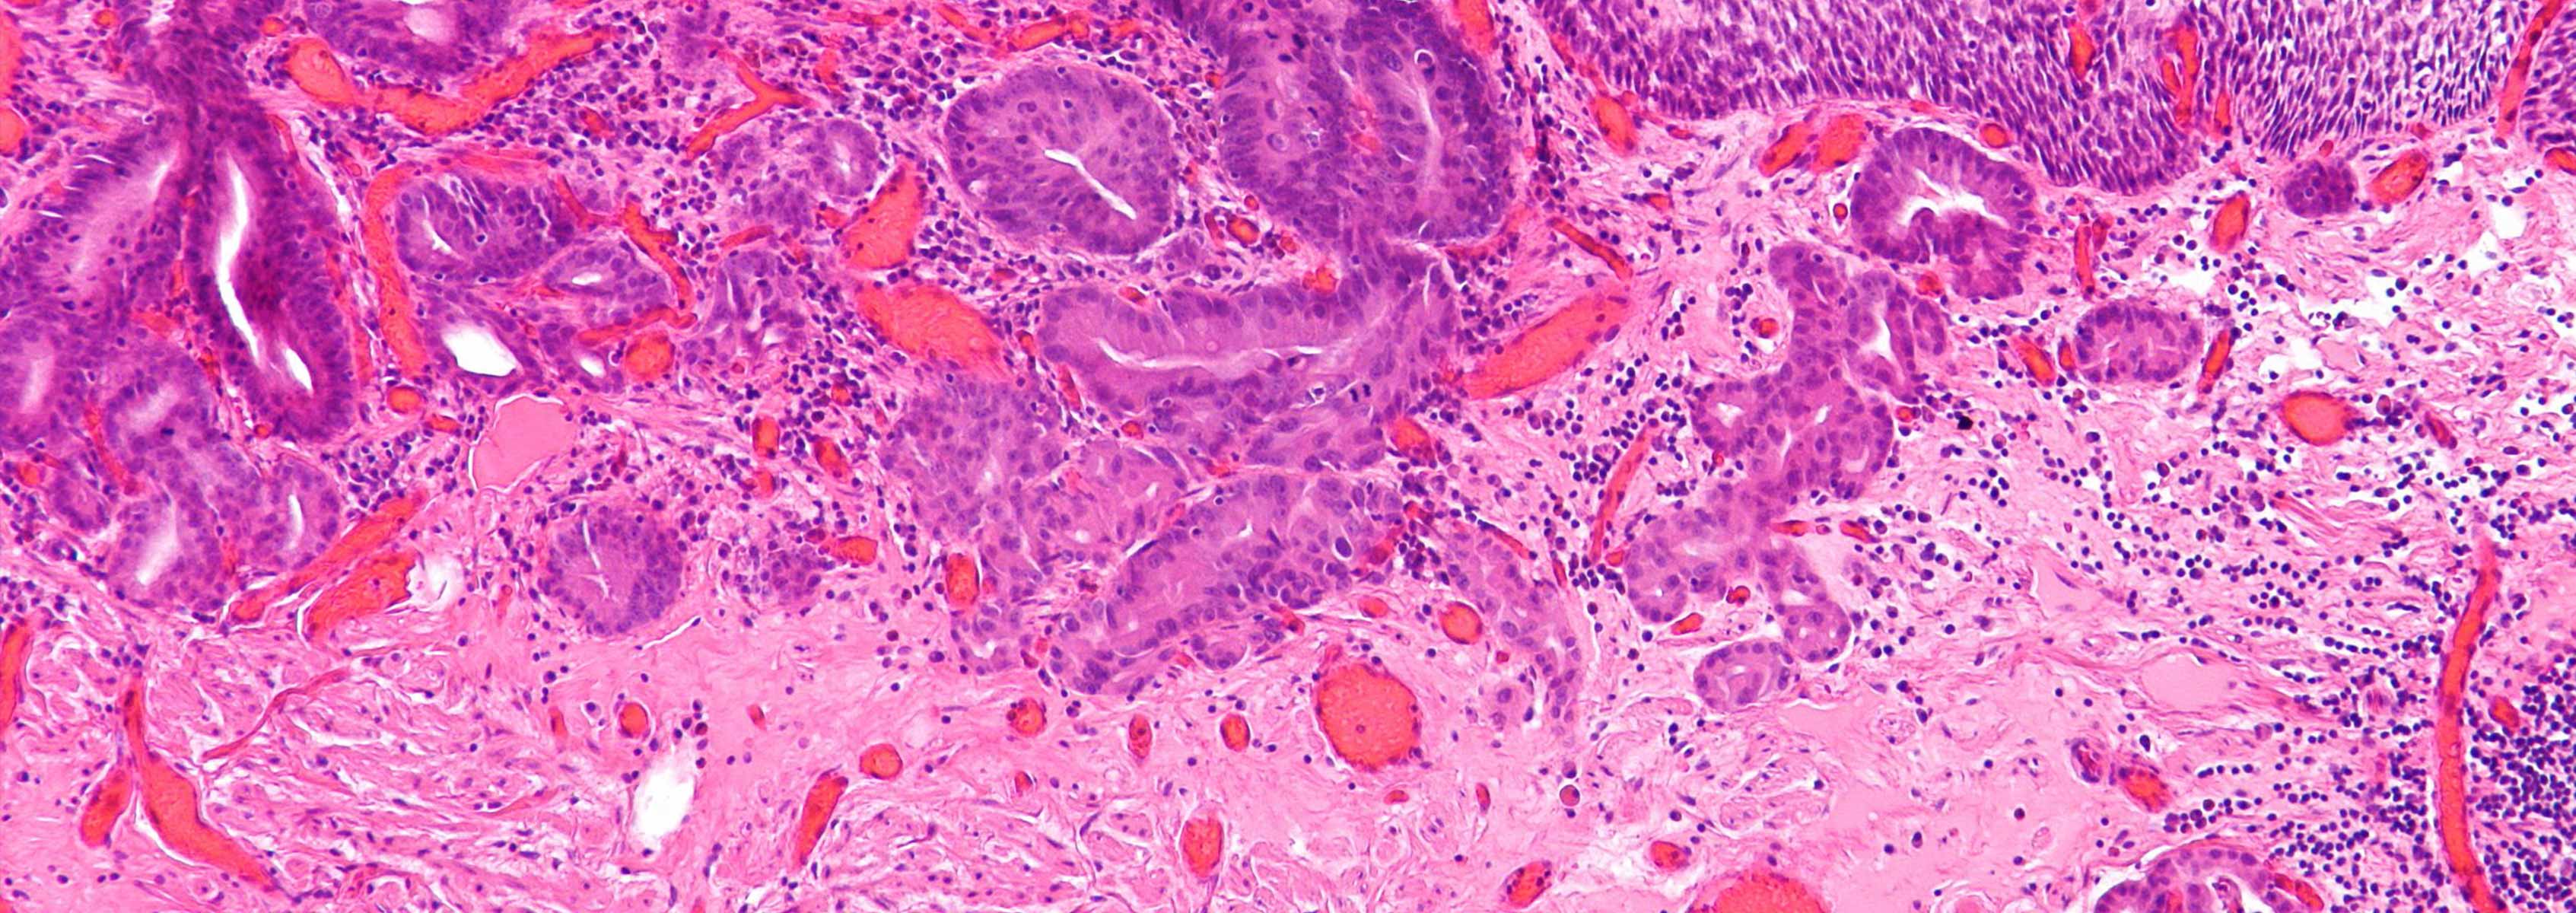

Progression of Esophageal Cancer

The distal esophagus is an important anatomic locus where gastric acid reflux causes several conditions that can lead to esophageal adenocarcinoma (EA), the incidence of which has increased 6-fold in the U.S. since the 1970s. The goal of this study is to investigate the microbial factors that contribute to the development of EA. We identified two different two types of microbiotas in the distal esophagus.